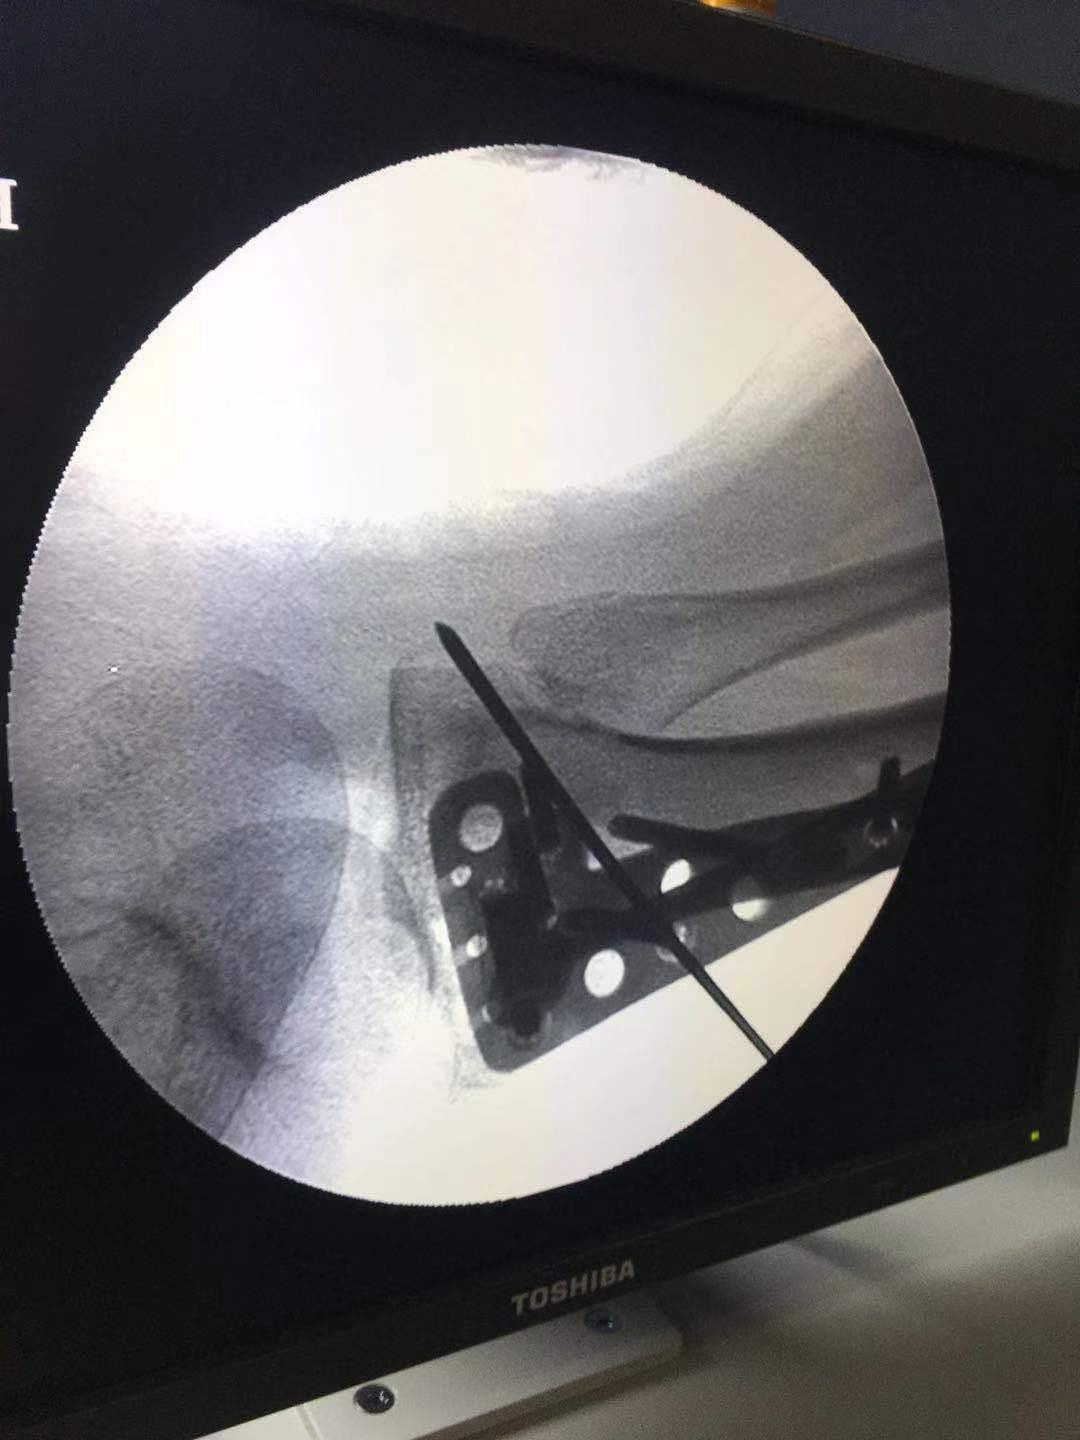

麻醉下行下肢牵引,同时对分离的胫骨平台进行手法复位。维持位置透视判断复位情况,及进一步调整牵引。

透视复位满意后临时固定。